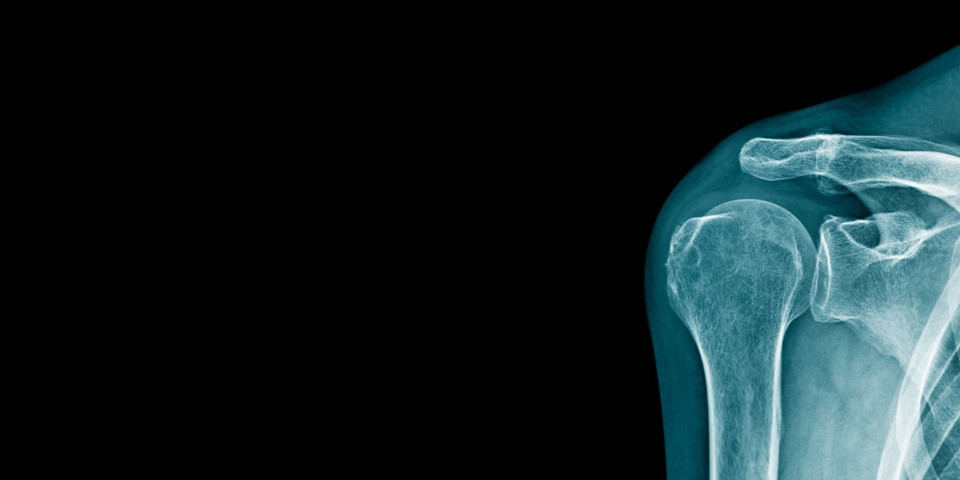

Weekend Warriors: Avoid Shoulder Dislocations

When an injury occurs, often times patients will notice sever pain and locking up of the joint. The shoulder contour may look abnormal. Seeking care immediately by a medical professional is important. Typically, these are injuries that require a visit to an emergency room and not an urgent care facility. The reason for this is the shoulder may require being put back in the socket and necessitates sedation and close monitoring which often times are not available at an urgent care facility. Sometimes these injuries can result in damage to ligaments, nerves, blood vessels and/or bones.